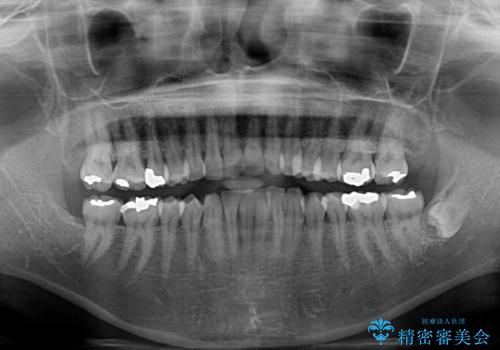

- 上下前歯のデコボコ改善をインビザラインにて行いたいとのことで来院された患者様です。

インビザラインをご希望のことで、IPR(歯と歯の間を削る)などによりスペースを獲得して、排列していくこととしました。

骨格的に上下顎が左右にずれていたため、正中位置は現状を維持したまま歯列不正を解消していくことになります。